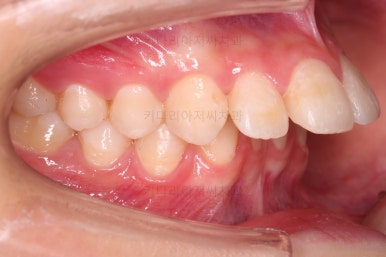

초진 시 입안의 모습입니다.

위아랫니가 많이 삐뚤진 않는데 뭔가 이상하죠?

어금니 맞물림은 지그재그로 잘 맞물려 있는데 위아래 앞니는 서로 앞뒤로 매우 멀죠.

비밀은 매우 자연스러워 보이지만 아래 앞니 2개가 선천 결손인 상태였습니다.

앞니가 매우 튀어나와 보이고요.

앞니끼리 맞물리지 않다보니 아래 앞니는 점점 솟구쳐 과개교합(깊게 맞물려 아래 앞니가 거의 보이지 않는 현상)이 되게 됩니다.